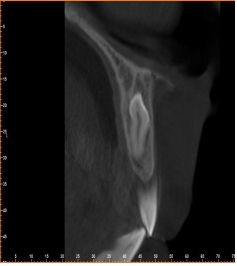

¸Åº¹µÈ °úÀ×Ä¡ÀÇ °æ¿ì¿¡´Â CT ÃÔ¿µ µîÀ» ÅëÇØ °úÀ×Ä¡ÀÇ Á¤È®ÇÑ À§Ä¡¸¦ È®ÀÎÇϰí

¼ö¼úÀ» ÇØ¼ °úÀ×Ä¡¸¦ ¹ßÄ¡ÇØ¾ß ÇÕ´Ï´Ù.

°úÀ×Ä¡ ¹ßÄ¡¼ö¼úÀº ¹ß°ß Áï½Ã ÇÏ´Â °ÍÀÌ ¿øÄ¢ÀÌÁö¸¸ »óȲ¿¡ µû¶ó ¹Ì·ç¾î¾ß ÇÒ ¼ö ÀÖ½À´Ï´Ù.